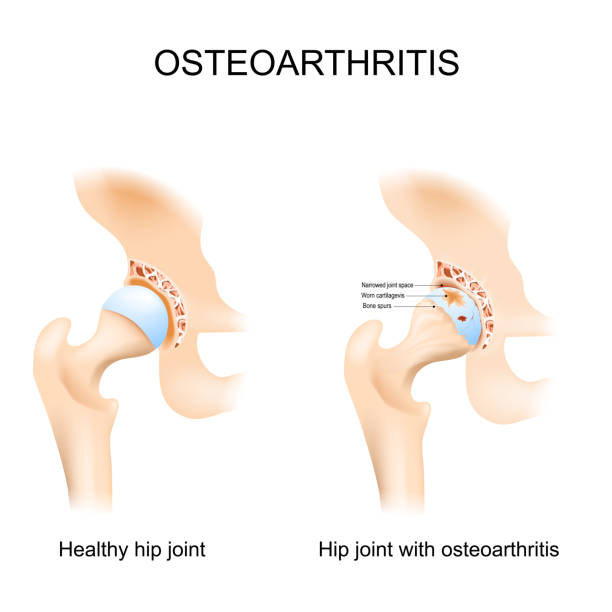

- Osteoarthritis

- It is a degenerative joint disease where the cartilage that cushions your bones gradually wears away.

- Common symptoms are stiffness, pain during movement, grinding sensation, reduced range of motion.

- It affects individuals over 50 or those with a history of joint injuries or obesity.

- It hurts when protective cartilage gone, bones rub against each other, causing inflammation and chronic pain. Bone spurs may also form.